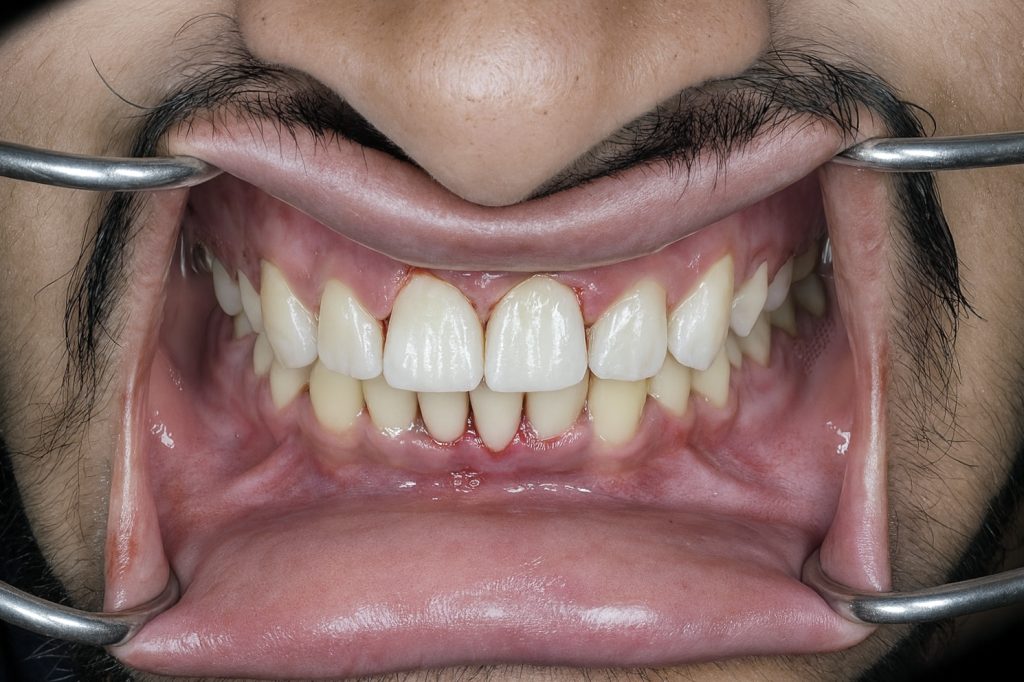

Outcome

- Invisible transition between tooth and composite

- Natural halo effect and depth recreated

- Increased brightness without over-whitening

- Strong adhesive interface thanks to enamel bonding

- Patient extremely satisfied with the natural, clean aesthetic